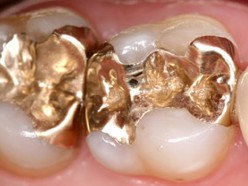

Gold

Goldgußfüllungen (Goldinlays) sind auch bei

sehr ausgedehnten Defekten die haltbarste Möglichkeit,

das "Loch" in einem Zahn wieder zu verschließen.

Die Lebensdauer hängt davon ab, ob der Zahn erneut

an Karies oder Parodontitis erkrankt. Die laborgefertigte

Goldgußfüllung selbst unterliegt einem so geringen

Verschleiß, dass sie lebenslang halten kann. |